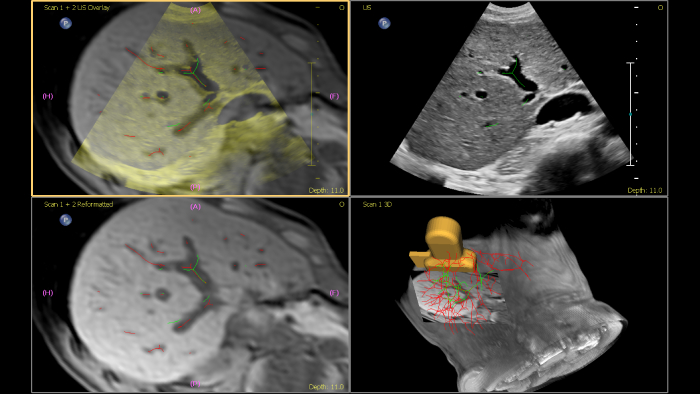

Os ecógrafos da Philips para a radiologia de intervenção suportam uma gama de capacidades sofisticadas para aplicações de intervenção. O fluxo de trabalho otimizado permite aos médicos alcançar uma fusão rápida e eficaz de TAC/RM/PET/CBCT com ecografia em tempo real, enquanto a navegação da agulha ajuda a orientar a biópsia e a ablação das lesões pequenas e de difícil acesso. A fusão e a navegação também podem ser utilizadas em conjunto com a ecografia com realce por contraste (CEUS), dando aos médicos acesso a ferramentas de diagnóstico ainda mais poderosas com visualização avançada.

Esta ferramenta semiautomatizada ajuda a delinear um contorno 3D à volta de uma estrutura de interesse, melhorando a orientação do procedimento mesmo em casos tecnicamente difíceis em que a lesão pode não ser visualmente óbvia ao nível de ultrassom. A lesão pode ser apresentada em 3D ou 2D através de uma modalidade complementar e sobreposta na ecografia ou TAC em tempo real, ajudando a visualizar a localização em relação às estruturas críticas circundantes.